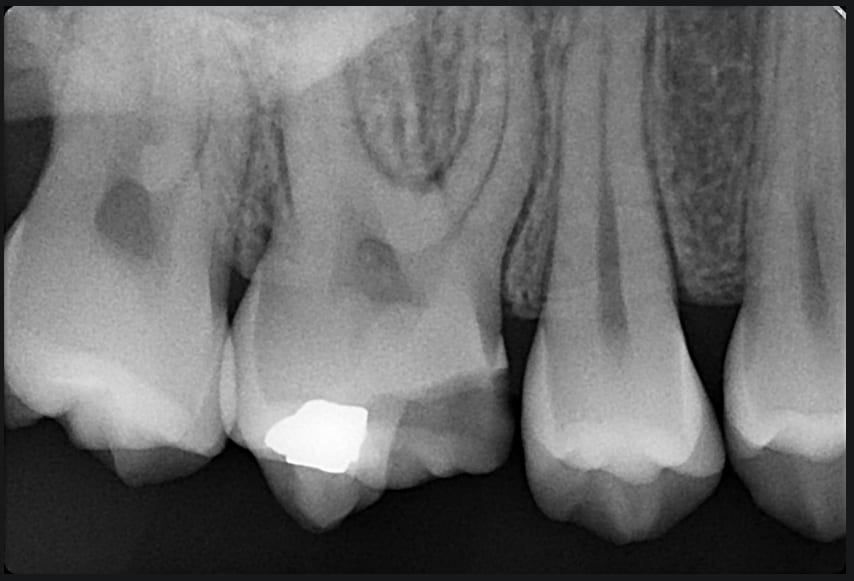

Pas plus tard que hier.

Une ado handicapée de 15ans, C2S, vu pour un deuxième avis après le devis pas piqué des hannetons chez une consœur.

900€ pour une étude esthétique et la réalisation d'une couronne avec... le risque que cela coute plus cher et de devoir dévitaliser la dent car la "carie" est profonde

Je vous joins la rétro...

Juste une fracture du pan MV de la 16. Le point de contact mésial est encore intact. Pas de trace de lésion carieuse.

La gamine est repartie avec un 3 faces des familles.

C'est pas chercher à attraper le nigaud ca ?